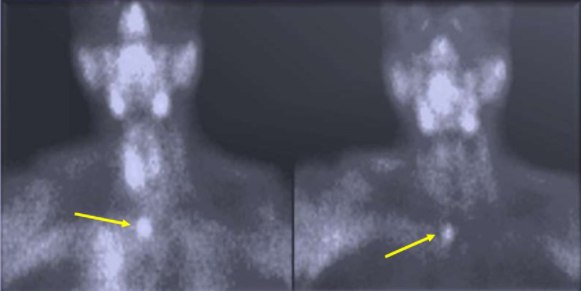

В некоторых случаях может понадобиться дополнительное обследование состояния сердечно-сосудистой системы, лёгких, почек и печени. При возникновении спорных вопросов, при метастазировании назначается проведение позитронно-эмиссионной томографии (ПЭТ) и субтракционной сцинтиграфии. Однако окончательно диагноз ставится после расшифровки результатов пункционной биопсии.